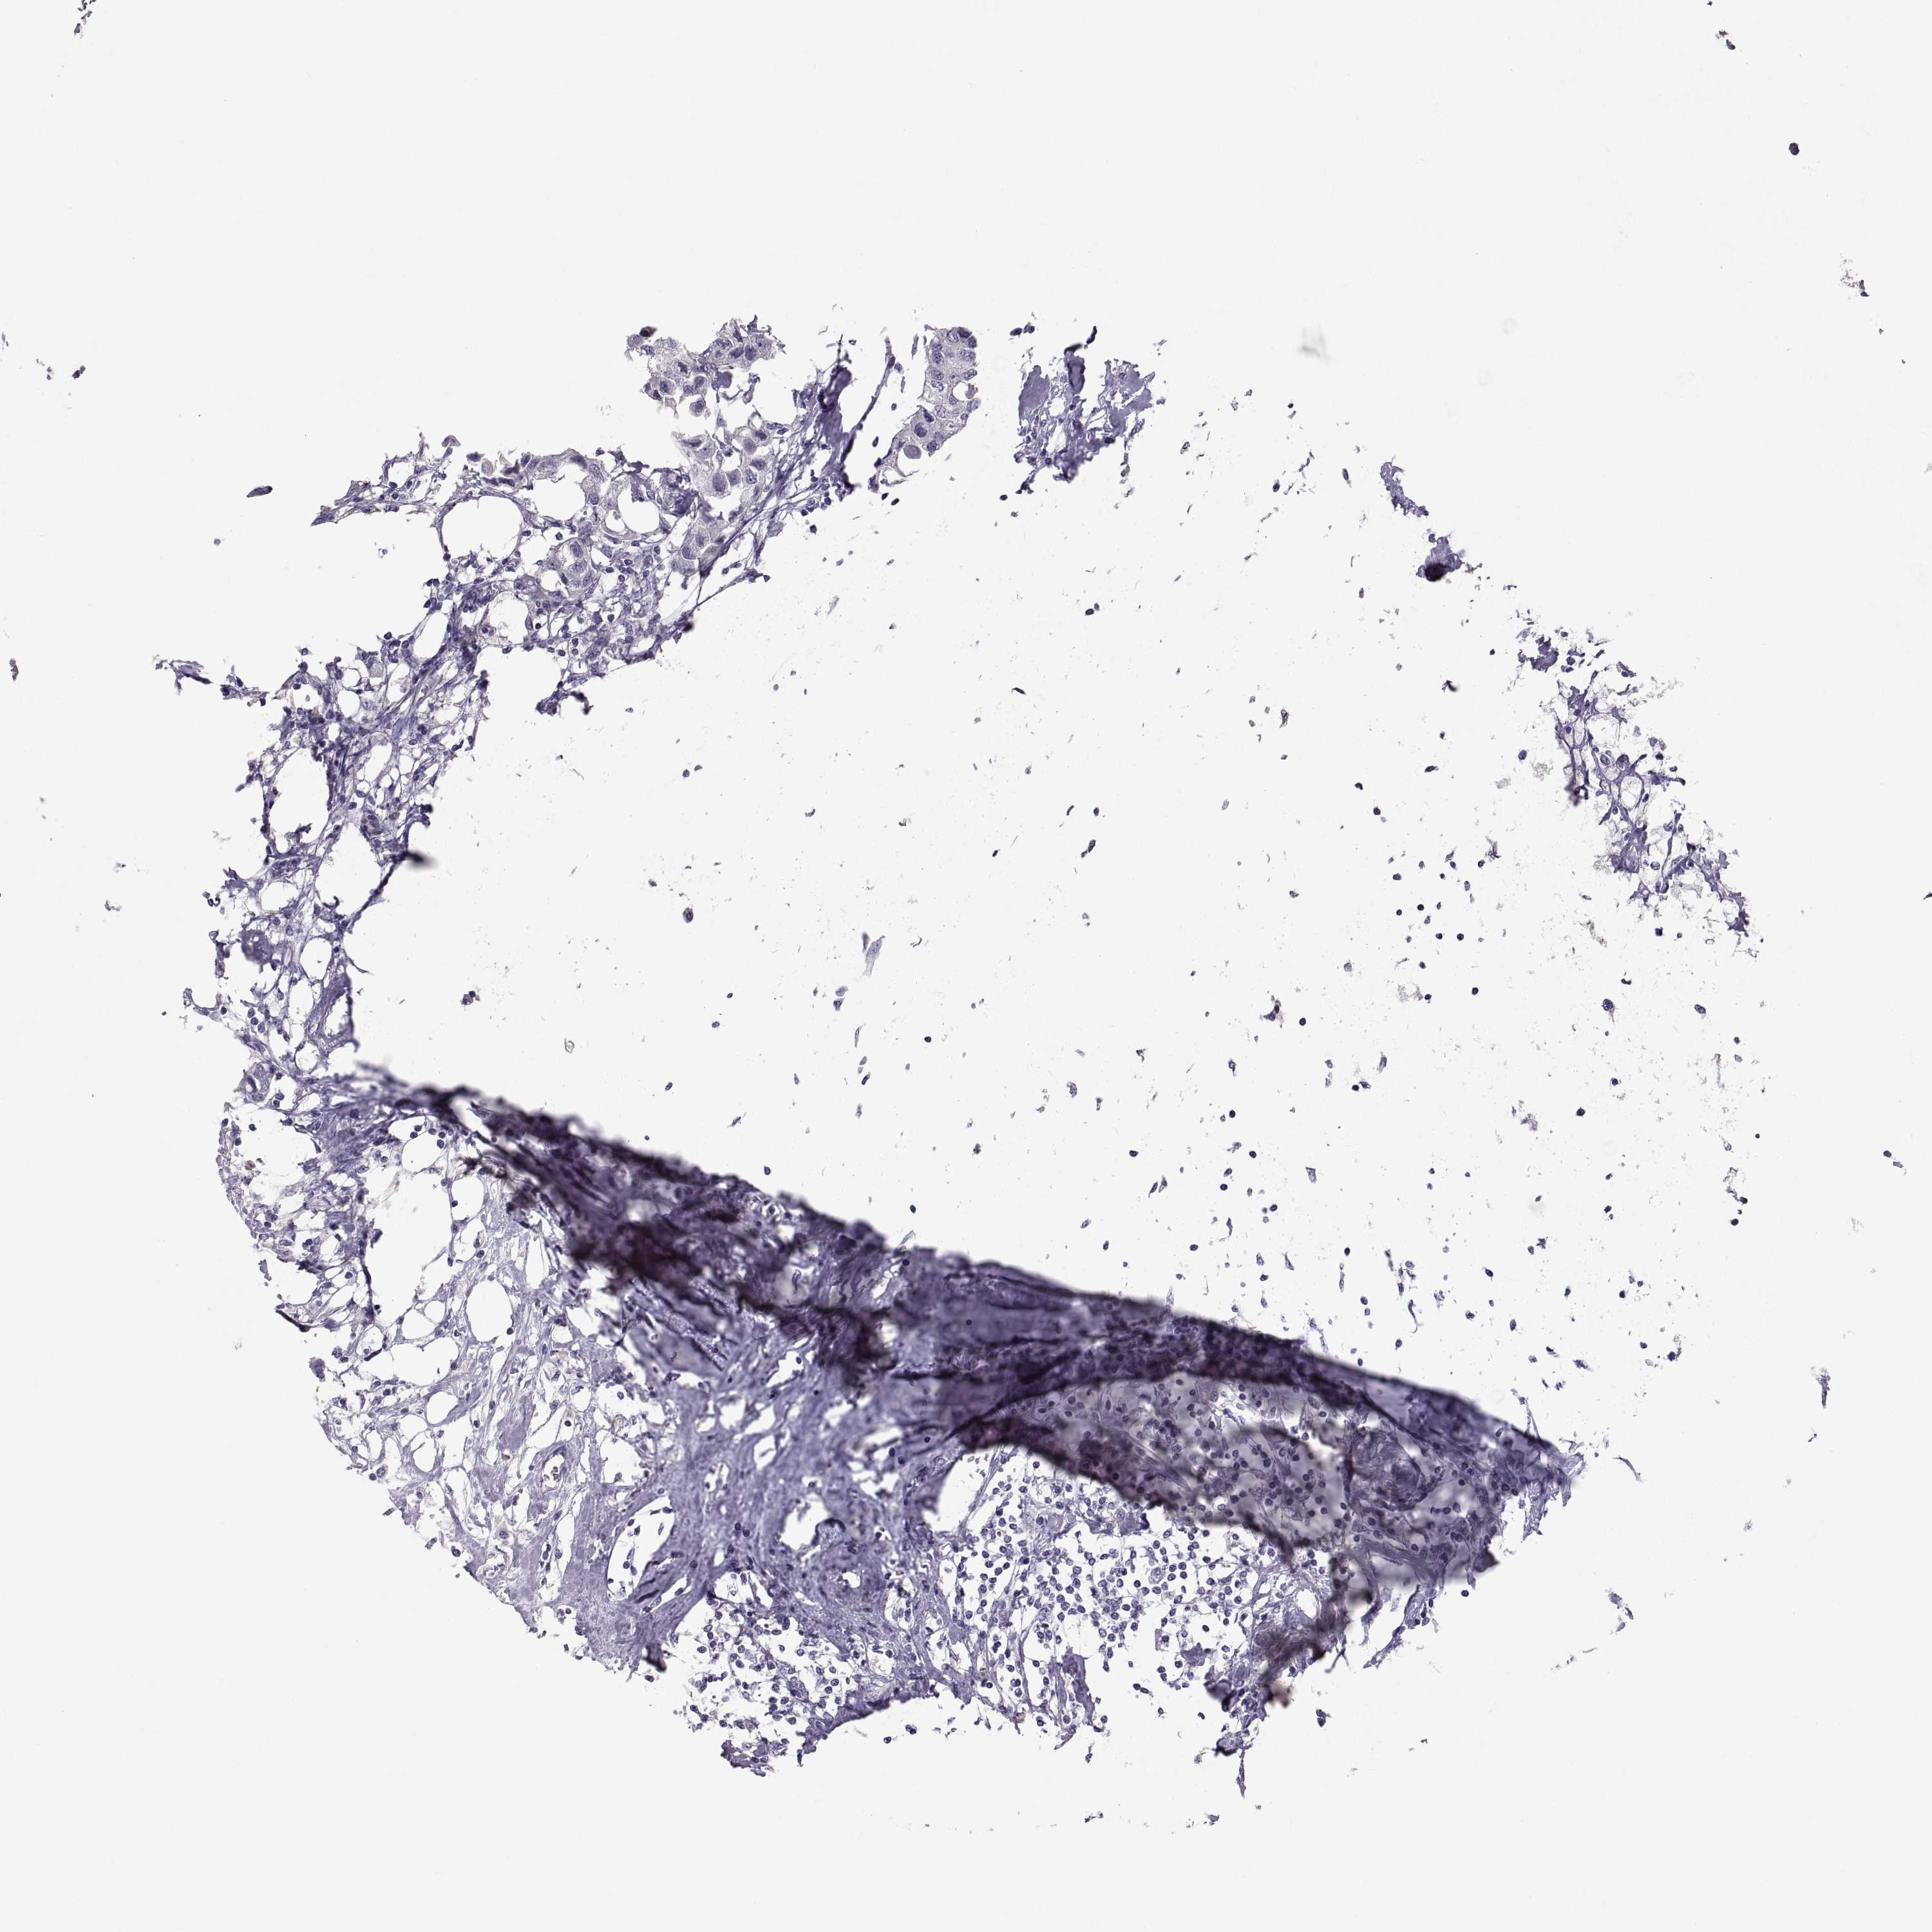

BRCA TCGA BRCA VALIDATION PROTEIN EXPRESSION

Breast cancer

Human cancer